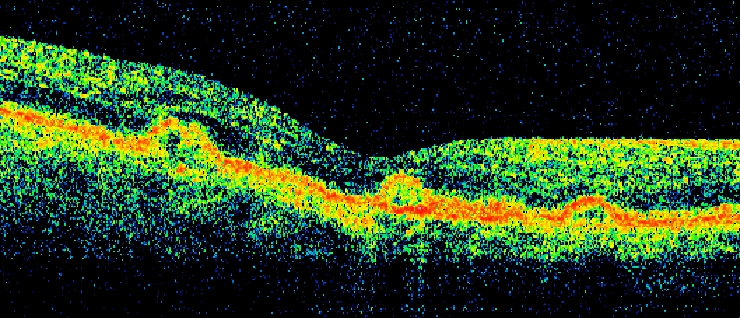

Sub-Retinal Fluid (SRF)

srf1

Sub-Retinal Fluid and

srf2